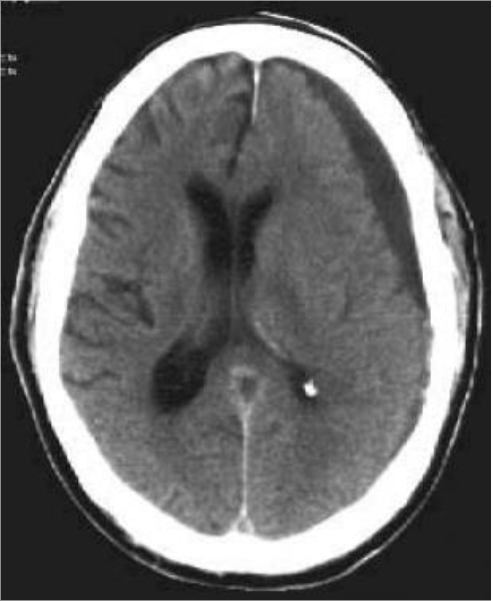

Questions 1-4 are based off the following two images:

Name the type of haemorrhage in each image.

Image 1: Subdural haemorrhage, Image 2: Extradural (Epidural) haemorrhage

Describe the shape of the haematoma in each image.

Image 1: Crescent, Image 2: Lentiform/Biconvex

What vessels are characteristically damaged in each image?

Image 1: Cortical bridging veins, Image 2: Middle meningeal artery

Other than shape and origin of bleed, what other characteristic distinguishes the above two bleeds from each other?

Subdural bleeds cross suture lines, extradural bleeds do not